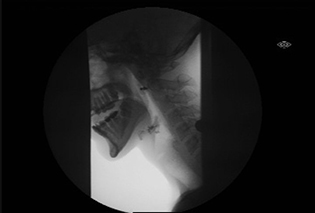

Normal MBSS

A picture of a modified barium swallow study for a normal patient.